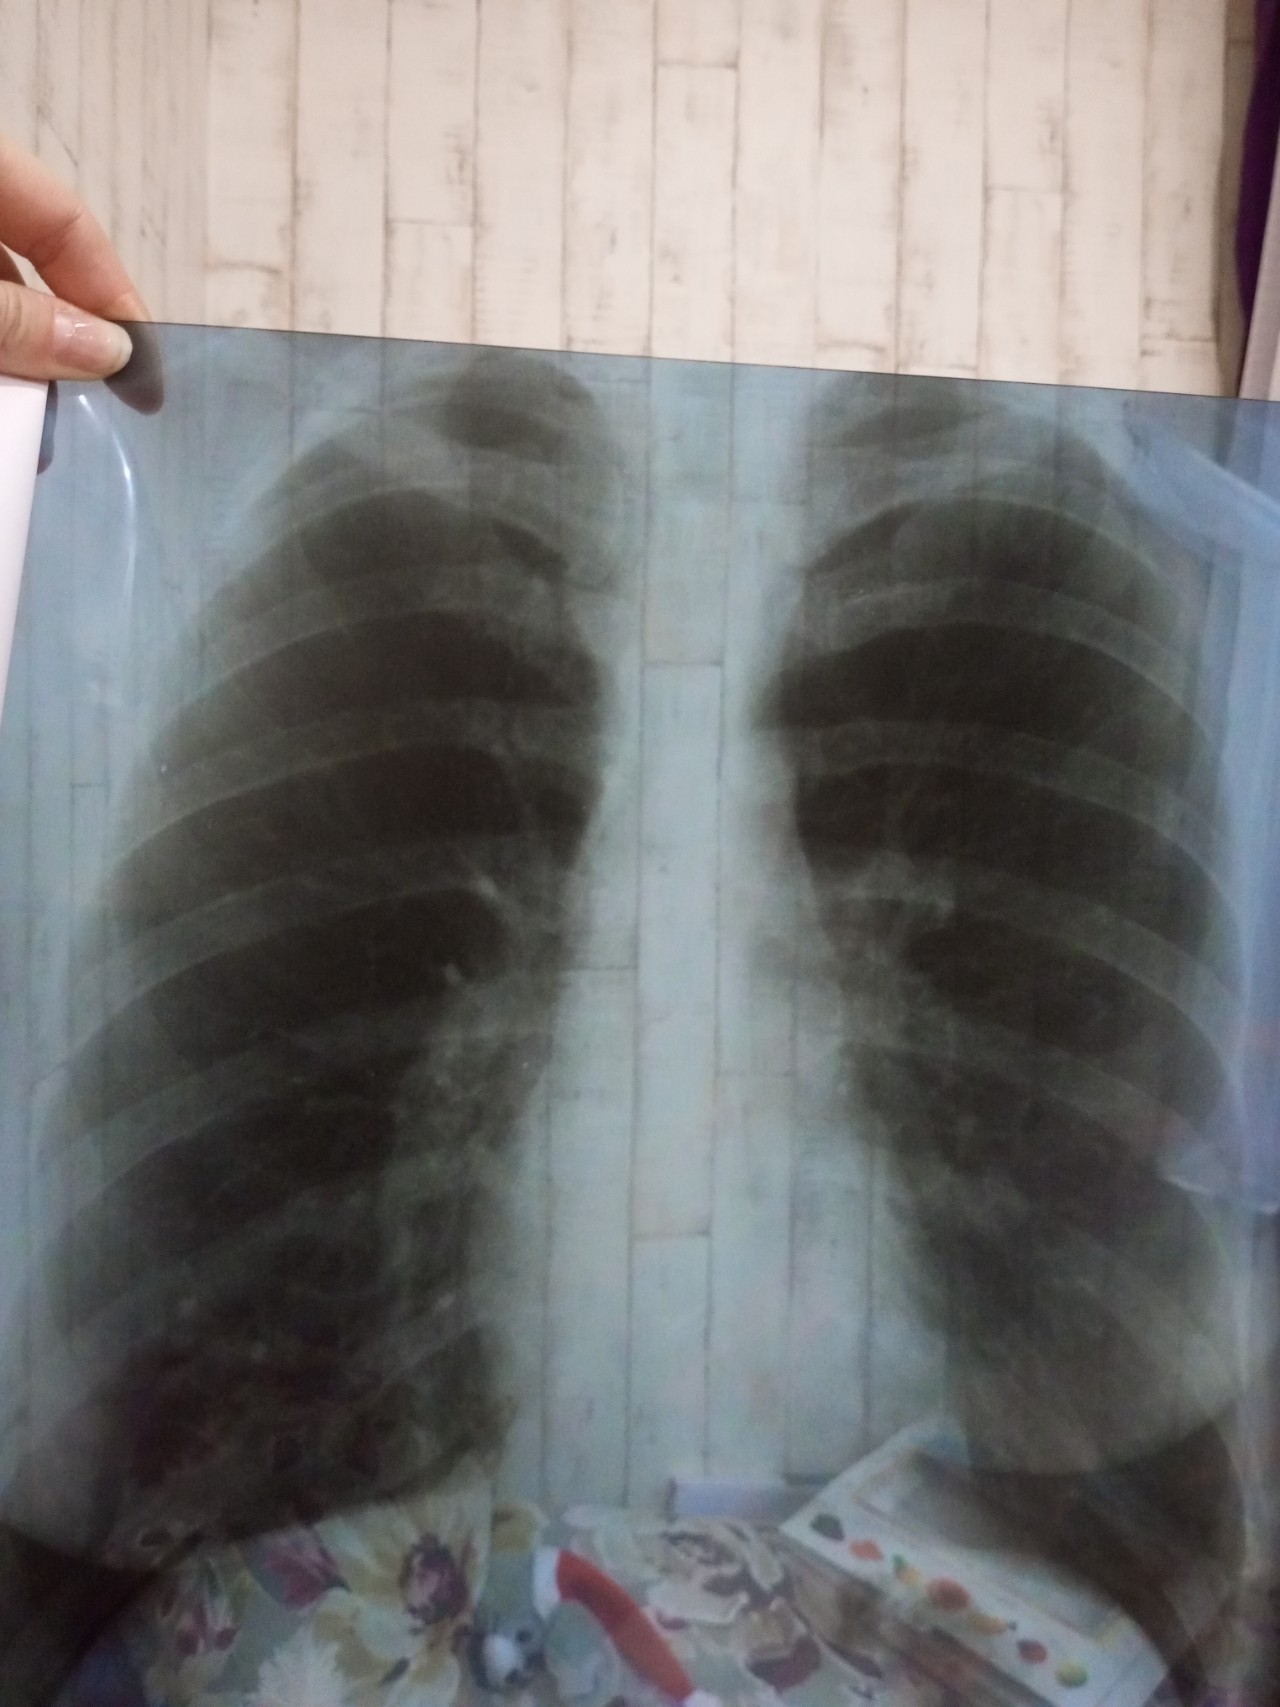

Фотографии, демонстрирующие обнаруженное усиление легочного рисунка

Раздел: Фотодневник открытий